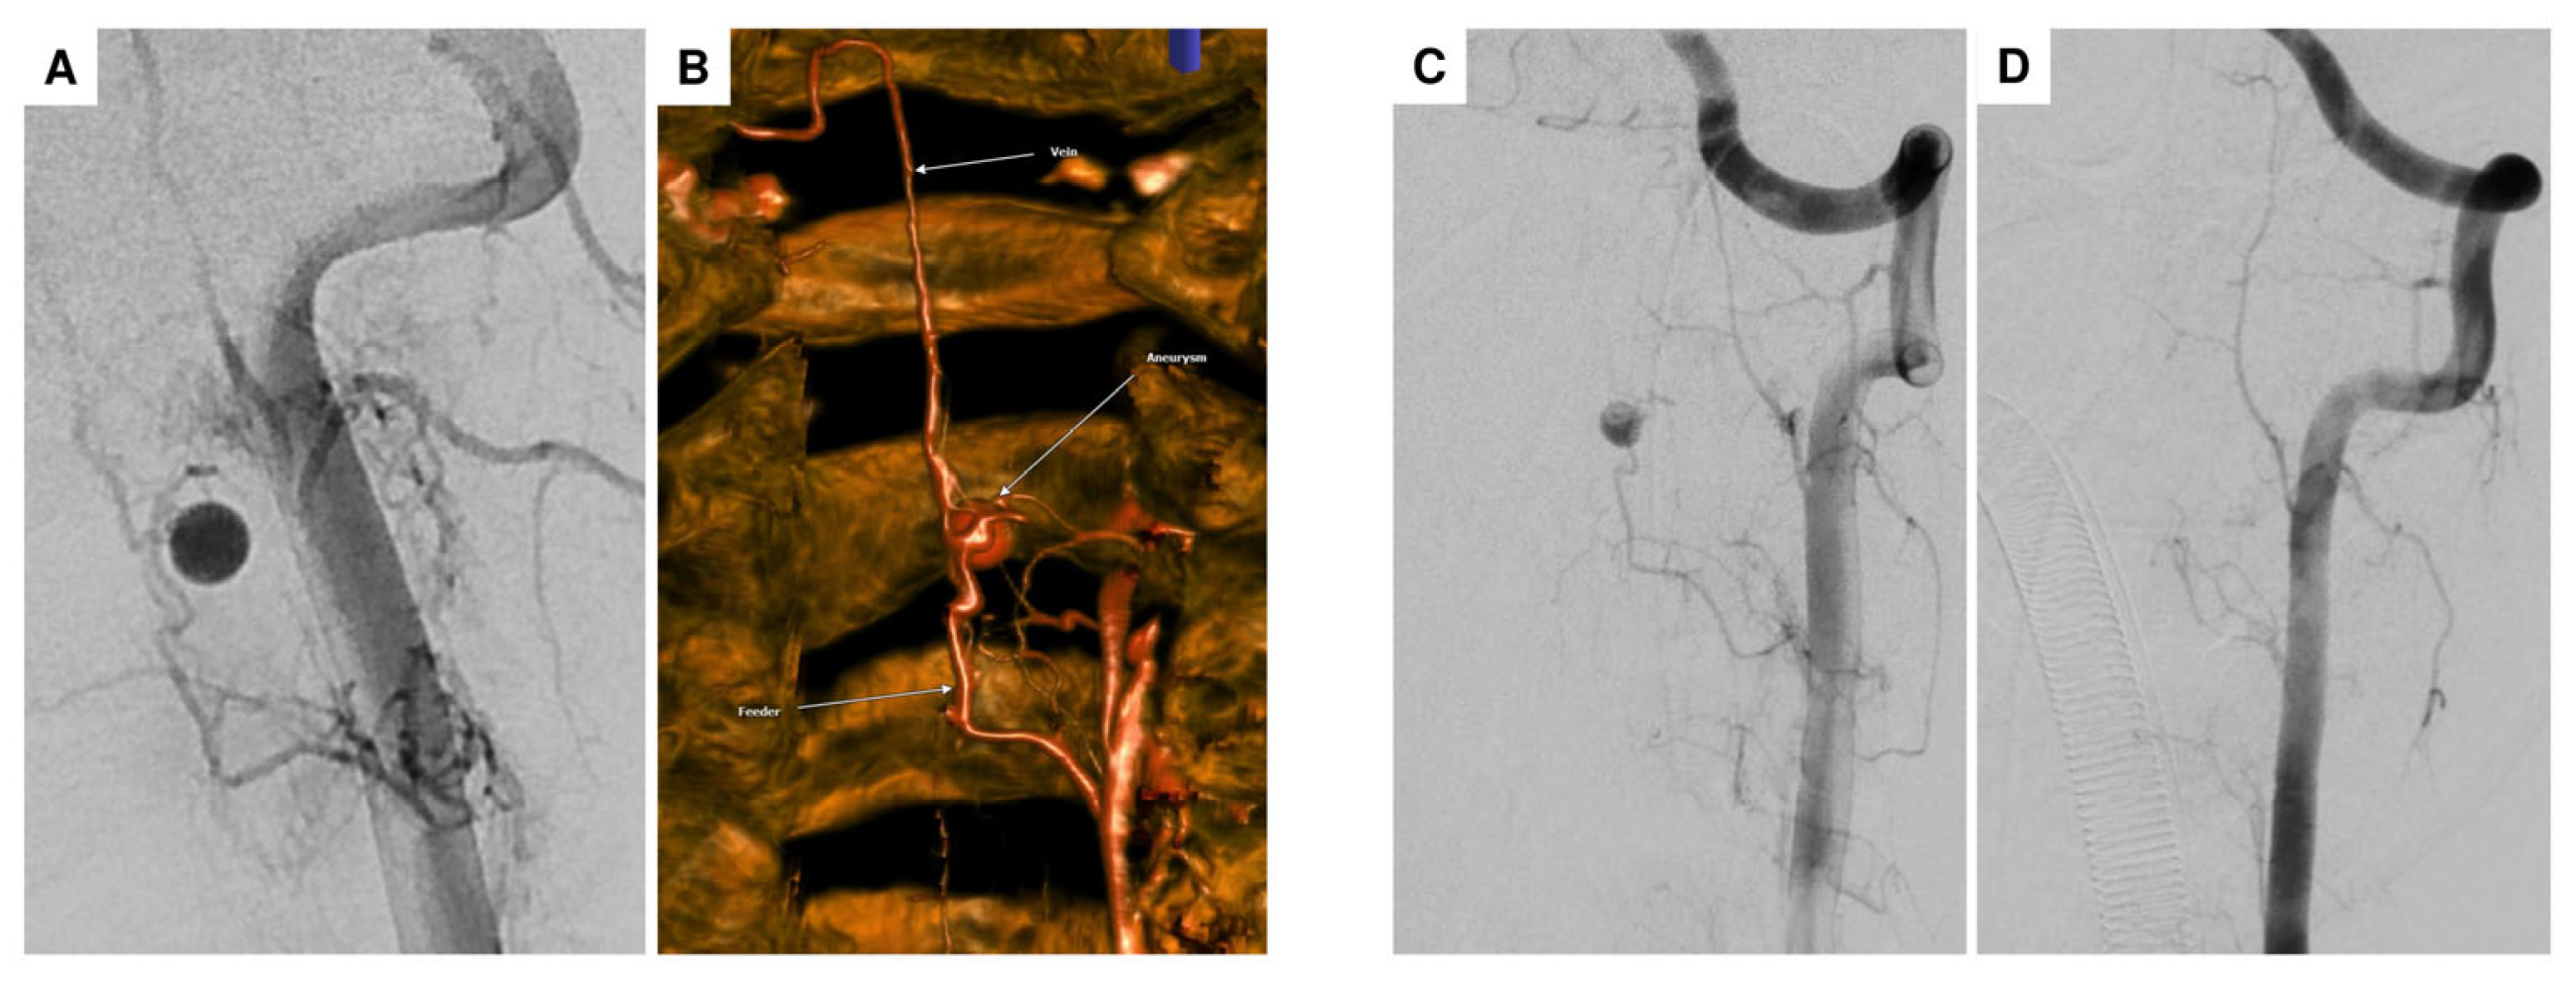

| 2 | F | 69 | headaches and abdominal complaints | oriented 3×, marked meningism, positive Lasègue sign | spinal SAH with (partial) thrombosed intraspinal aneurysm at T2 | aneurysm | multiple DSA, multiple spinal MRI | surgical procedure (resection of the aneurysm) |